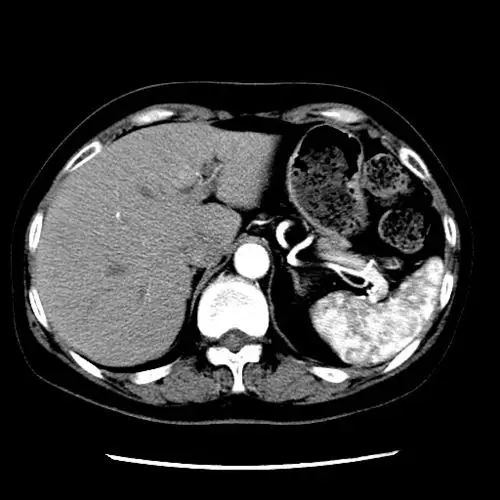

【求助】左肾积水(无功能),腹膜后一包快 [病例帖]